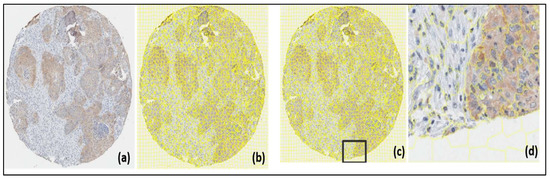

- SLIC super pixel construction: Groups of pixels that share features like color, brightness, or texture are known as super pixels. In addition to offering an easy starting point from which to compute image characteristics, they also considerably reduce the complexity of subsequent image processing operations. Histopathological pictures have shown it to be effective [20].

- Experimentation: The SLIC method was applied to the original (untransformed), normalized, and histogram equalization TMA images using ImageJ with the jSLIC plugin [20], which corresponds to a computationally more efficient variation of SLIC but retains the original method. To begin with, jSLIC is basically governed by two parameters, which are:

3.1. SLIC Super Pixels